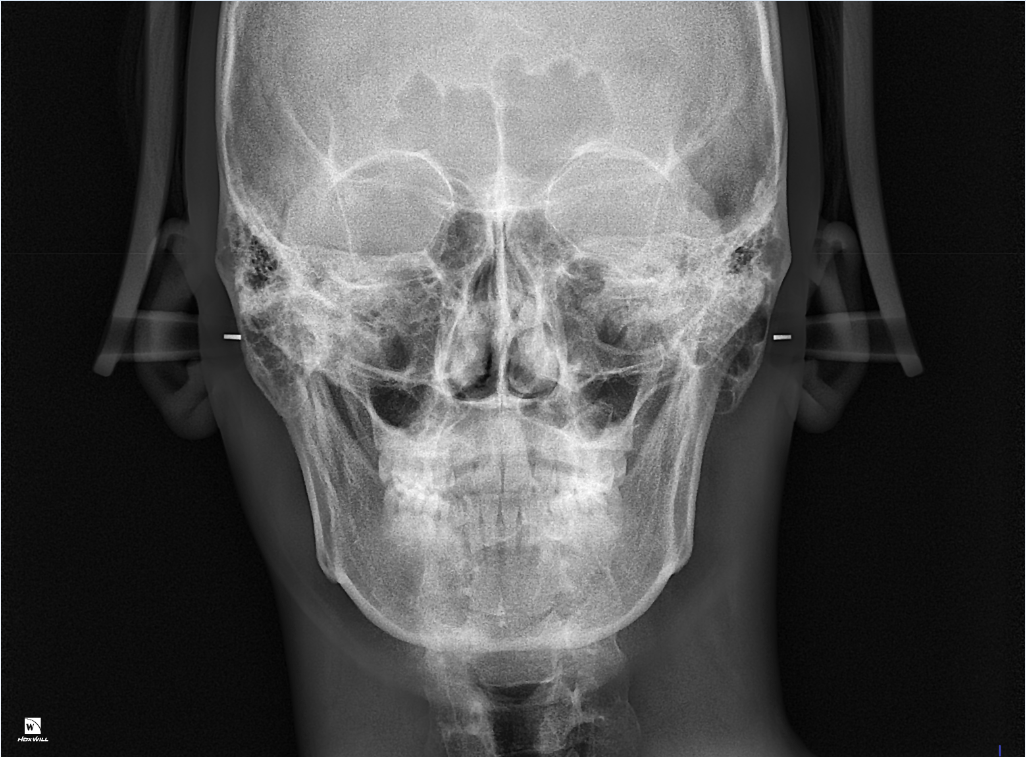

약간 비대칭이 있긴한데... 치아중심선 맞추기랑 앞니 부분적으로 절단교합이 있어서 교정할려고 해요

인비절라인으로 하면 1년 정도면 된다고 하는데 투명교정 하게되면 치아중심선이랑 12번치아 앞니 교합 교정, 전체적 치아가 살짝 틀어진거 교정 효과 볼 수 있을까요?

• 3번 째 사진